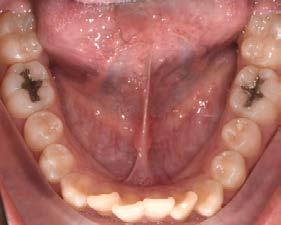

Caries y pérdida dental

La formación de caries en la dentición decidua y la consecuente pérdida prematura de órganos dentales deciduos, en algunas ocasiones, son

consideraciones a tomar muy en cuenta como factor etiológico en la inclusión del canino (Figura 32).

Por un lado, la presencia de caries interproximales en dientes deciduos, ya sea de manera independiente o como consecuencia de caries rampantes en uno o varios dientes, propicia la disminución de la longitud y/o perímetro del arco dental, donde ya no habrá, en consecuencia, el espacio necesario para el acomodo definitivo de los caninos y premolares permanentes.14

Por otro lado, al haber una pérdida prematura de un diente deciduo, además de generar una disminución de la longitud del arco dental, la biomecánica fisiológica propia de nuestro organismo, tiende a cerrar los espacios o brechas generadas por la pérdida de algún órgano dental, mesializando los dientes distales al diente faltante y generando extrusión del antagonista inmediato (Figura 33).